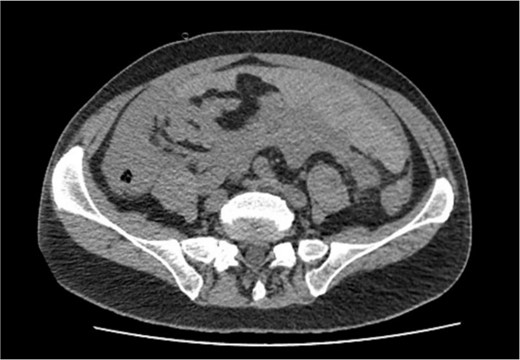

Non-contrast abdominal computed tomography (CT) revealed hemoperitoneum: moderate ascites with organized clot on the surface of greater omentum (Fig. 1)

Computed tomography image on admission: moderate ascites with organized clot.